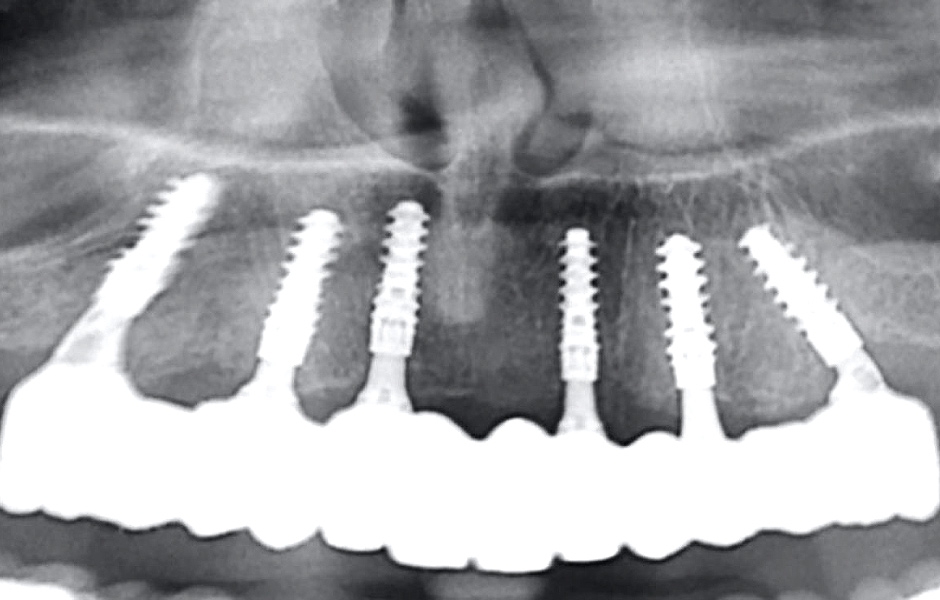

Definitivní náhrada byla nasazena a ověřena z hlediska estetiky, okluze a funkce (obr. 51–55). Panoramatický kontrolní snímek potvrdil, že všechny parametry protetického ošetření odpovídají očekávaným hodnotám (obr. 56).

Při kontrole po 18 měsících po dokončení ošetření bylo provedeno intraorální, extraorální a radiografické vyšetření. Nebyly zjištěny žádné patologické nálezy a výsledné parametry zůstaly stabilní (obr. 57–62).

Obr. 56

Obr. 57